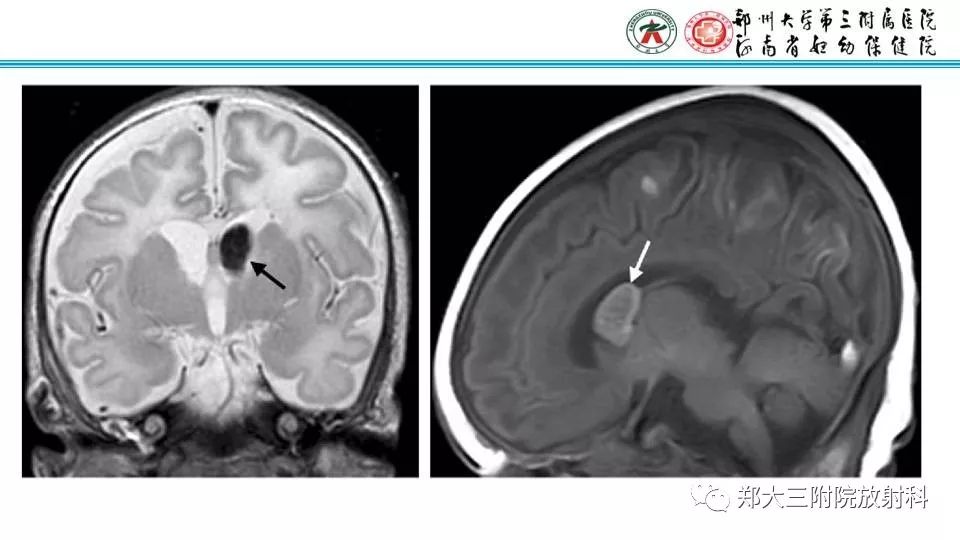

【PPT】室周假性囊肿-1